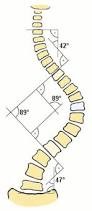

Omurgada ne gibi sorunlar olabilir?

Omurgada kaymalar olabilir, omurgada kırıklar olabilir, omurgada eğrilikler kifoz veya skolyoz olabilir. İşte bu sorunlar derecelerine tespit

Skolyoz ve kifoz cerrahisinde riskler daha fazla ve çıkabilecek komplikasyonlar çok daha fazladır.Bu gelişebilecek erken veya geç